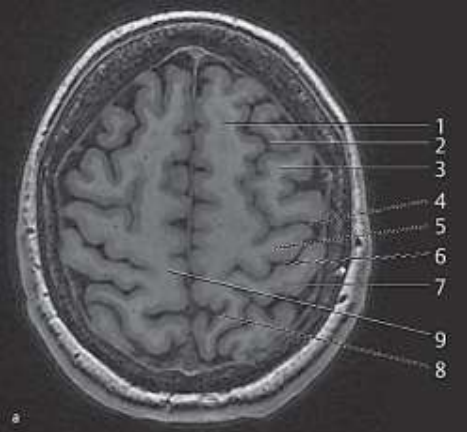

Com base na imagem de ressonância magnética a seguir e seus conhecimentos de neuroanatomia radiológica, assinale a alternativa que descreve corretamente o nome e a função da estrutura indicada pelo número 5